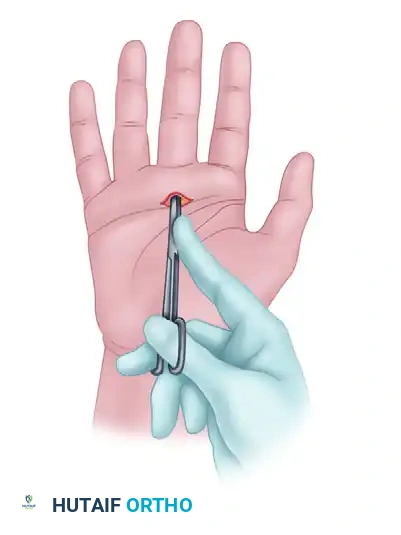

Figure: Standard transverse incision markings for open surgical treatment of trigger finger.

- Hyperextend the metacarpophalangeal joint to stretch the A1 pulley and displace the neurovascular bundles dorsally.

- Insert a 19-gauge needle just distal to the flexor crease. The bevel of the needle must be oriented longitudinally, parallel with the tendon fibers.

Figure: Initial percutaneous needle insertion.

Figure: Percutaneous release of long finger A1 pulley. Metacarpophalangeal joint hyperextended and 19-gauge needle inserted just distal to the flexor crease. Skin markings indicate the path of flexor tendons.

- Stabilize the needle and use the sharp bevel to sweep and release the pulley from proximal to distal.

- A distinct loss of grating sensation as the pulley is cut indicates the completion of the release.

Figure: Needle stabilized and pulley released from proximal to distal.